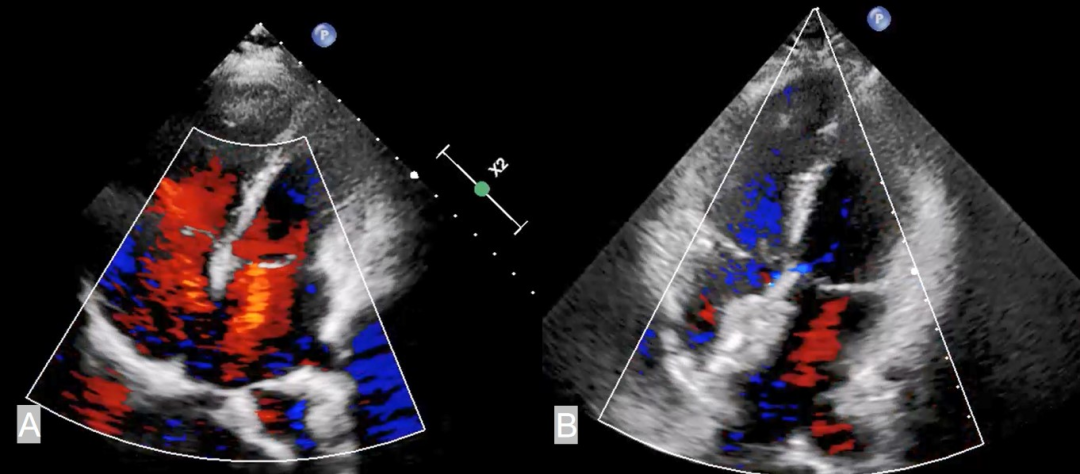

病例1是一名33岁的女性,因反复胸闷气促1年就诊,心超提示有28mm的继发孔型房缺,肺动脉收缩压高达98mmHg,右心导管检查提示患者的平均肺动脉压力为48 mmHg,PVR为5.4 Wood U,Qp/Qs=1.8。经过6个月的双联肺动脉靶向药物治疗,患者的PASP仍高达80mmHg,随后升级为三联(马昔腾坦+利奥西呱+司来帕格)治疗,6个月后封堵尝试失败。因此,我们为患者行PADN治疗,在肺动脉主干与左肺动脉交接处行射频消融治疗,术后随访2个月,患者的平均肺动脉压力降至40 mmHg,PVR为3.2 Wood U,Qp/Qs=2.6。最后成功用32mm的房缺封堵器进行了封堵,封堵术后3个月心超随访PASP成功降至43mmHg。

病例2是一名29岁的女性,反复胸闷气促1年余,心超提示15mm大小的继发孔型房缺,肺动脉收缩压达66mmHg,右心导管检测结果提示平均肺动脉压力为46 mmHg,PVR为7.59 Wood U,Qp/Qs=1.6。经过一个月的三联靶向药物治疗,心超的PASP仍高达65mmHg,因此,我们为患者行PADN治疗,在肺动脉主干与左肺动脉交接处行射频消融治疗,术后患者的平均肺动脉压力降至35 mmHg, PVR降至3.9 Wood U,最终成功用26mm的封堵器进行封堵。